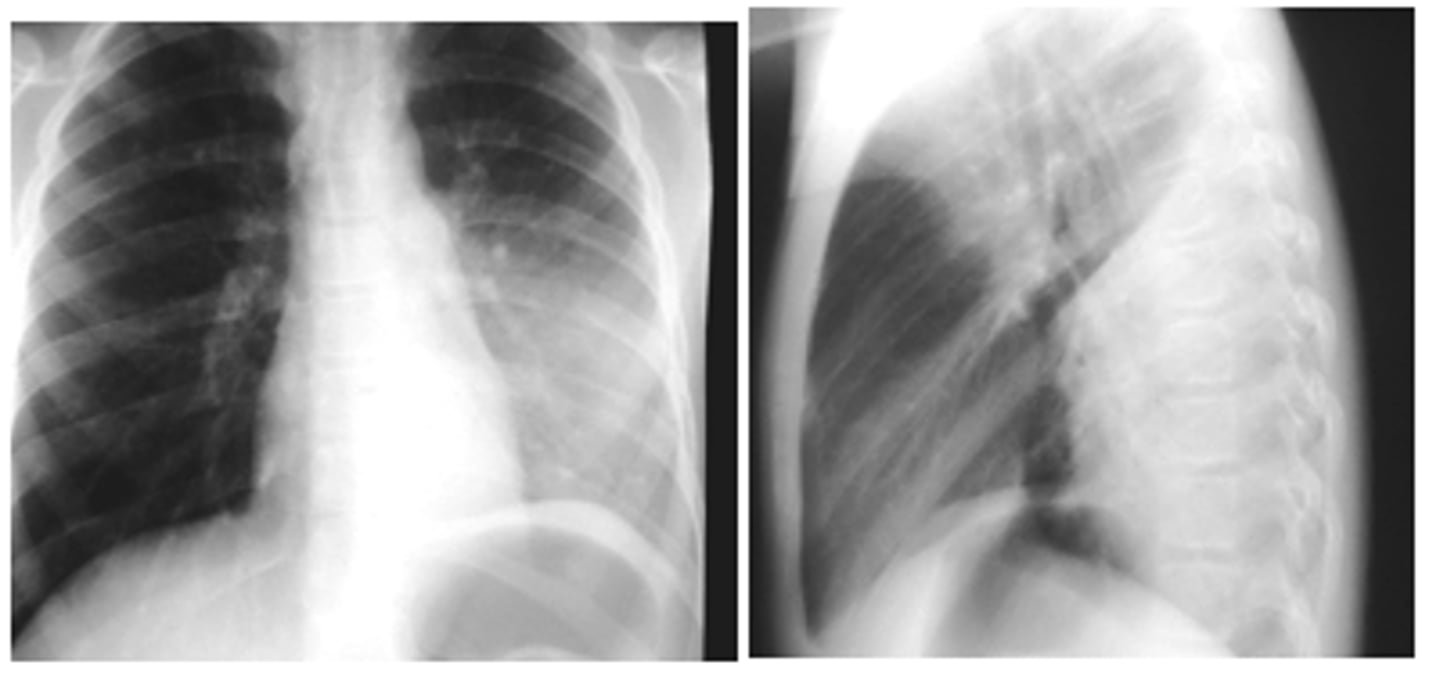

ID sign on back and finding

RML pneumonia obscuring the cardiac border but not the R hemidiaphragm. Note the triangular density on the lateral view.

<p>RML pneumonia obscuring the cardiac border but not the R hemidiaphragm. Note the triangular density on the lateral view.</p>